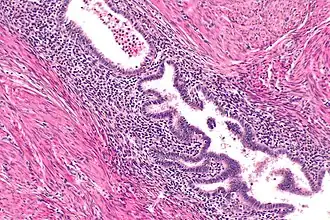

Gallbladder adenomyomatosis is a benign disease of the gallbladder characterized by hyperplasia of the mucosal epithelium and smooth muscle cells inside the muscularis propria.[4][5][6] The excessive proliferation of epithelial cells causes the mucosa to invaginate into the muscular layer lining the gallbladder wall, resulting in characteristic diverticula known as Rokitansky-Aschoff sinuses. These sinuses may be filled with biliary sludge, cholesterol crystals, or gallstones.[4][5][6]

There are three morphologic variants described in the literature – diffuse, segmental, and localized.[5][6] Diffuse, also known as generalized, adenomyomatosis has a widespread distribution of hyperplastic changes and thickening across the gallbladder wall.[5][6] The localized form of adenomyomatosis is also known as a gallbladder adenomyoma (in a similar manner that uterine adenomyoma is the localized variant of adenomyosis). The localized form is a single mass, typically in the fundus, that protrudes into the lumen of the gallbladder in the form of a polyp.[5][6] The segmental form is characterized by its annular (ring-shaped) distribution of adenomyomatosis in the body of the gallbladder, often giving it an hourglass-like appearance.[5][6]

Ultrasound is the preferred initial diagnostic choice for suspected gallbladder disease. Several distinct features of adenomyomatosis are discernable using ultrasound, making it a reliable modality for diagnosis.[4][5][6] The most characteristic features seen on ultrasound are the Rokitansky-Aschoff sinuses, which present either as echogenic foci when filled with biliary sludge/gallstones or anechogenic foci when filled with normal bile.[4][5][6] Other key features that may be seen include wall thickening and ring-down artifacts known as "comet tails" (produced by reverberations of sound between the sinuses).[4][5][6] Ultrasound can also distinguish between diffuse, segmental, and localized variants of adenomyomatosis based on morphology.[5][6]

In some cases, gallbladder wall thickening may be seen on ultrasound but is poorly defined and lacking specificity, particularly if the characteristic Rokitansky-Aschoff sinuses are not visualized. This can make it difficult to distinguish adenomyomatosis from other conditions that result in gallbladder wall thickening such as gallbladder cancer.[4][5][6] In these cases, MRI can prove helpful in providing the resolution needed for diagnosis. Especially effective is the T2-weighted MRI at visualizing the pathognomonic Rokitansky-Aschoff sinuses, which appear as round-shaped hyperintense cystic spaces that align in a curvilinear fashion along the gallbladder wall in a pattern described as the ”pearl necklace sign”.[4][5][6]